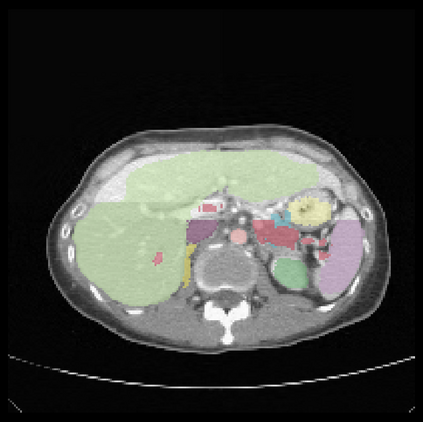

It is imperative to ensure the robustness of deep learning models in critical applications such as, healthcare. While recent advances in deep learning have improved the performance of volumetric medical image segmentation models, these models cannot be deployed for real-world applications immediately due to their vulnerability to adversarial attacks. We present a 3D frequency domain adversarial attack for volumetric medical image segmentation models and demonstrate its advantages over conventional input or voxel domain attacks. Using our proposed attack, we introduce a novel frequency domain adversarial training approach for optimizing a robust model against voxel and frequency domain attacks. Moreover, we propose frequency consistency loss to regulate our frequency domain adversarial training that achieves a better tradeoff between model's performance on clean and adversarial samples. Code is publicly available at https://github.com/asif-hanif/vafa.